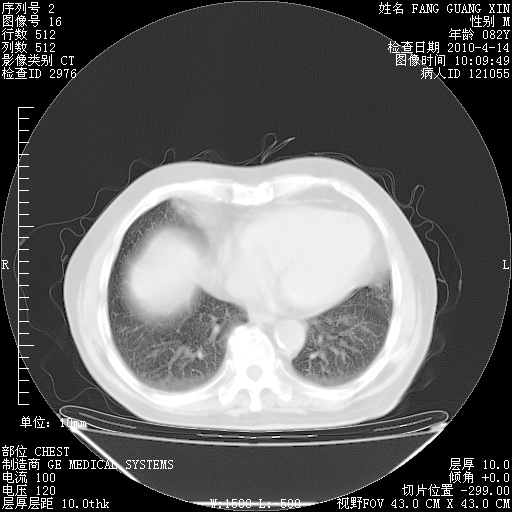

肺部CT平扫未见异常。